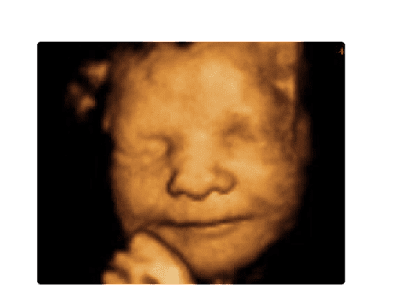

Ecografía 3D y 4D en Medellín

Discover cutting-edge women's health services at MediMujer in Medellin. Specializing in 3D/4D ultrasounds and vaginal plastic surgery, they offer advanced technology and expert care for all your reproductive health needs. Trust MediMujer for compassionate, professional treatment.